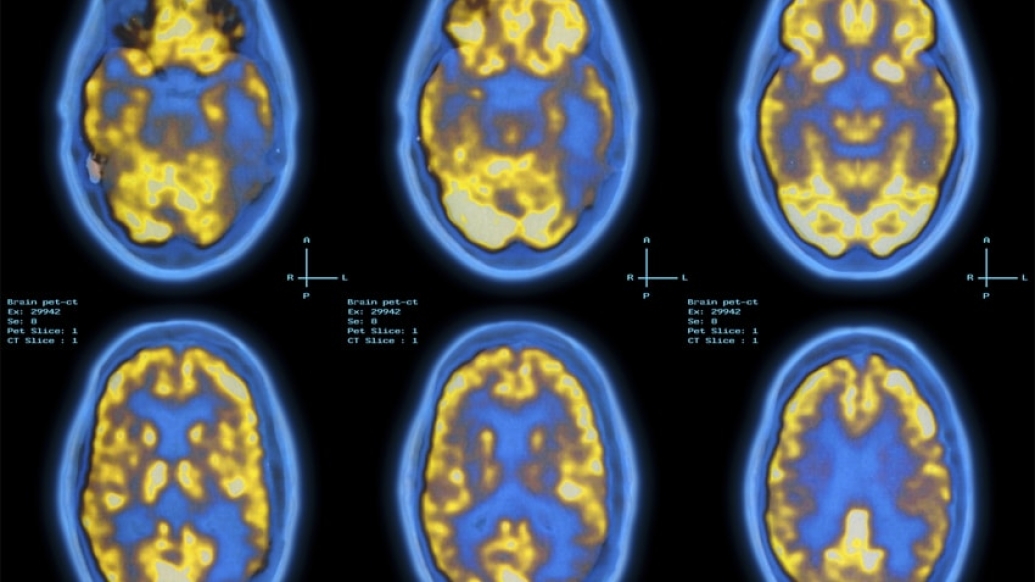

Funded by the biotech company Biogen, the study reported an experimental drug, called aducanumab, greatly reduced plaques in the brains of early-stage Alzheimer's disease patients. Plaques have long been targeted as the chief drivers of cell death and tissue loss — and in turn, impairment — in Alzheimer's patients. Stopping plaque buildup may be key to halting the disease's progression.

Heidebrink: The study shows how impressive this particular compound is at removing the amyloid plaque from the brain. Brain scans measuring amyloid plaque buildup before and after treatment showed a very consistent effect of aducanumab — the higher the dose, and the longer the treatment, the greater the effect. At the end of the study, the group who received the highest dose had scans so improved one could barely call them abnormal anymore. The effect was powerful.

Heidebrink: This is a preliminary study. It's great that the amyloid scans look better, but we really need to know how and if this drug could help our patients. This study was not designed to look at clinical effects, but there was a suggestion that people receiving the drug had less cognitive decline than people on the placebo. This needs more research, so that's why the U.S. Food and Drug Administration granted it fast-track designation to the next step.